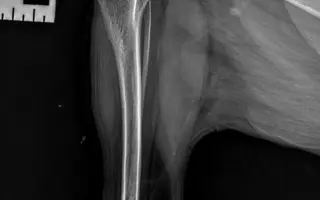

Fotogalerie